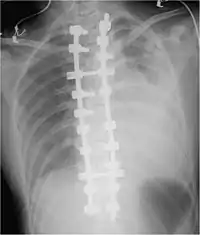

تصوير صدري بالأشعة السينية يُظهر تدمي صدري كبير في الجانب الأيمن